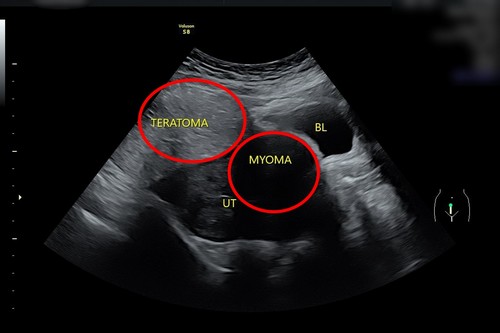

「子宮肌瘤、卵巢瘤同時發生,其實不常見」李佩蓁醫師表示,陳小姐卵巢瘤約十公分、子宮肌瘤約七公分左右,其中卵巢瘤已經大到在肚臍的位置就能摸得出來,而子宮肌瘤也不止一顆,還有其他小顆的肌瘤,這也造成她嚴重貧血。

左圖:婦科超音波顯示陳小姐同時有子宮肌瘤(右圈)及卵巢瘤(左圈)。